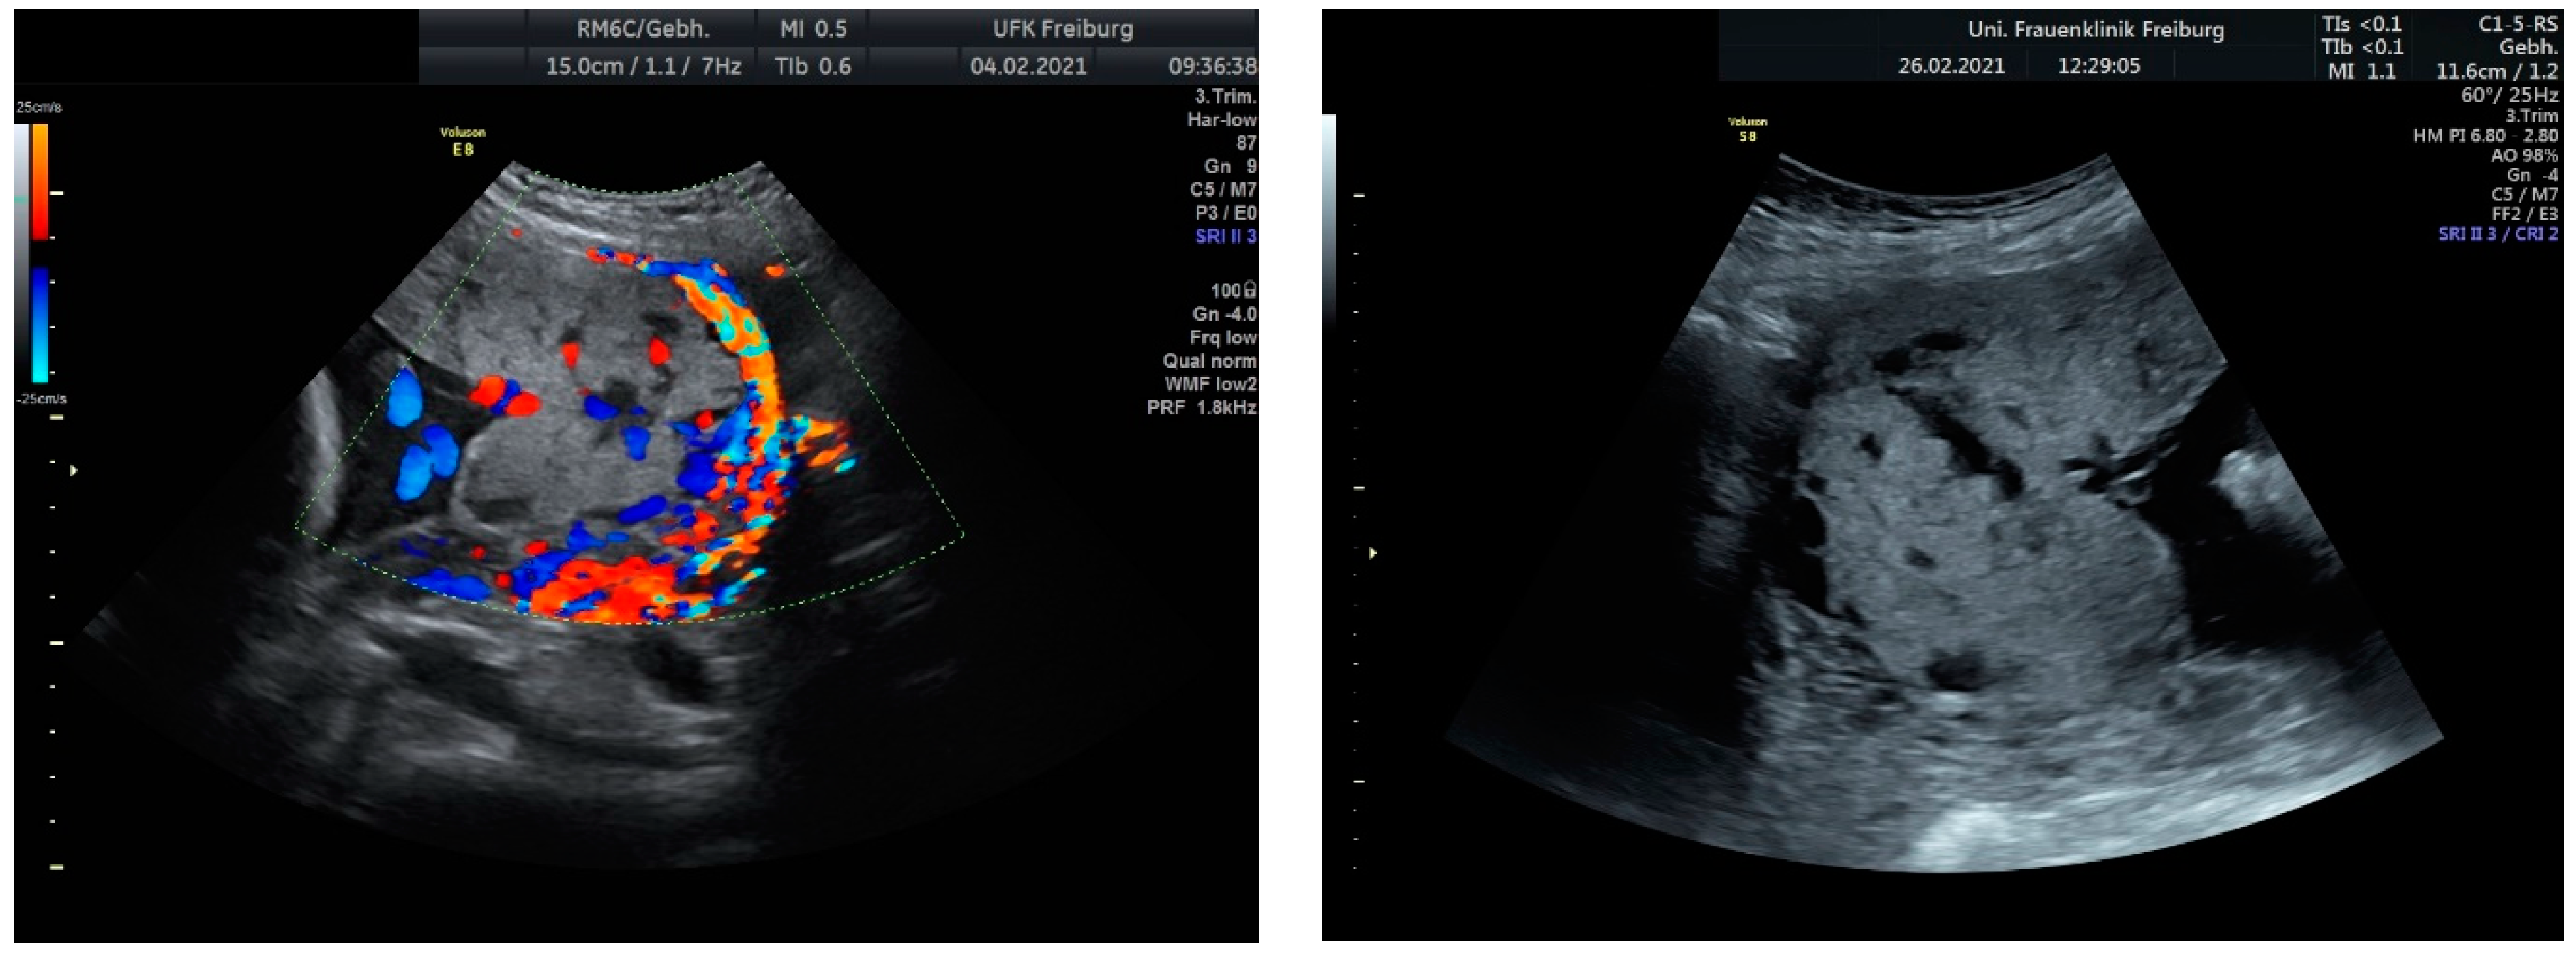

Sonographic findings (Figure 11):

Figure 11.

Increased placental blood flow on 2D ultrasound. Red color represents increased placental blood flow moving to the transducer; blue color represents placental blood flow moving leaving away from the transducer.

Sonographic findings (Figure 12):

Figure 12.

Enlarged vascular spaces within the placenta; A focal mass invading the myometrium, suggestive of placenta accreta; Hypervascularity noted at the interface between the serosa (outer uterine layer) and bladder.

These findings are characteristic of placenta accreta, a condition where the placenta attaches too deeply into the uterine wall, potentially leading to complications such as excessive bleeding during delivery. The hypervascularity at the serosa–bladder interface indicates the abnormal and increased blood flow associated with this condition. These imaging findings are crucial for diagnosis and guiding management decisions in cases of placenta accreta.